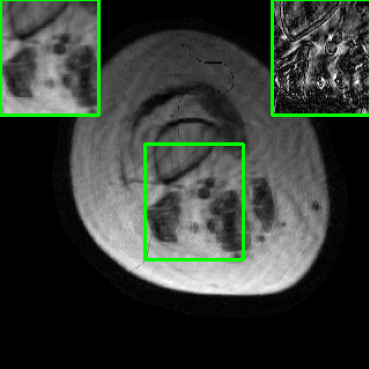

Performance on Data with Lesions: While the previous experiment allowed comparing reconstruction quality with or without planted features, here we test our method on MRI scans with lesions, which are often regions of abnormal or diseased tissue. We utilize the annotated fastMRI+ data666https://github.com/microsoft/fastmri-plus/tree/main to evaluate our method’s image reconstruction capabilities, and compare its outcomes with established baselines. For the training phase, the non-lesion dataset was employed for the global training approach with images whereas LONDN-MRI used adaptively selected images for training (searched from images). In contrast, during the testing phase, we used scans with lesions. The results, as displayed in Table V, indicate that our method achieves substantially higher PSNR values in comparison to the globally trained baseline as well as the LORAKI method. Furthermore, visualizations in Figure 16 clearly demonstrate the superiority of our method, particularly in the nonspecific white matter lesion areas. Thus, both in terms of visual assessment and PSNR values, our approach outperforms the existing baselines and aligns more closely with the ground truth.

| Ground Truth | LORAKI | Global | LONDN-MRI | LONDN-MRI | Oracle |

| (1 iteration) | (2 iterations) | ||||

![]() |

| PSNR = dB | PSNR = 31.45 dB | PSNR = 32.15 dB | PSNR = 32.72 dB | PSNR = 33.15 dB | PSNR = 33.22 dB |

| PSNR = dB | PSNR = 33.17 dB | PSNR = 35.10 dB | PSNR = 35.67 dB | PSNR = 35.74 dB | PSNR = 35.87 dB |

| PSNR = dB | PSNR = 33.21 dB | PSNR = 36.12 dB | PSNR = 36.31 dB | PSNR = 36.54 dB | PSNR = 36.71 |